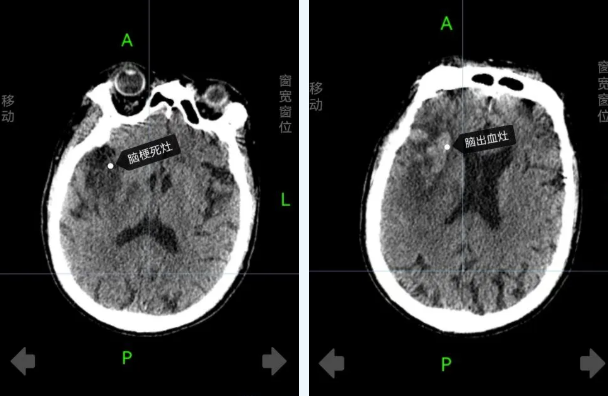

患方认为:新疆某医院康复科、放射科存在误诊误治。患者在新疆某医院某路院区放射科做了核磁检查。康复科、放射科在核磁共振片子明显提示病人脑出血的情况下出现了严重的误诊误治,康复科给病人使用脑出血禁忌药依诺肝素,口服阿司匹林肠溶片和氯吡格雷。

神经内科病程上清楚地记录了CT检查结果,诊断:急性脑血管病,脑出血。所以,新疆某医院某路院区放射科、康复科出现严重误诊误治。依据《中华人民共和国侵权责任法》第五十七条,医务人员在诊疗活动中未尽到与当时的医疗水平相应的诊疗义务,造成患者损害的,医疗机构应当承担赔偿责任。

第二、患者后期诊断明确,诊断为:(1) 右侧额颞顶大面积脑出血并破入脑室 (2)蛛网膜下腔出血 (3)右侧额颞顶大面积脑梗死 (4)脑疝。诊断依据:我院某路院区头颅MR提示右侧额顶亚急性脑梗死,移动CT提示:右侧额颜顶大面积脑出血并破入脑室、蛛网膜下腔出血;(5)术前查体提示患者昏迷,双孔散大,光反射消失,气管插管,呯吸机辅助呼吸。

至于为何有出血依然使用了阿司匹林等抗凝药物,医院回应:患者是急性脑血管病,混合型脑卒中(有大面积脑梗塞、也有出血),使用抗凝治疗并无不妥。

临床上,脑梗后又合并出血一般称为急性脑梗死后出血转化,它一直是很麻烦的问题,因为这两个治疗方案截然不同的疾病竟然碰在了一起。其出现的明确的机制尚不完全清楚,需要深入研究。